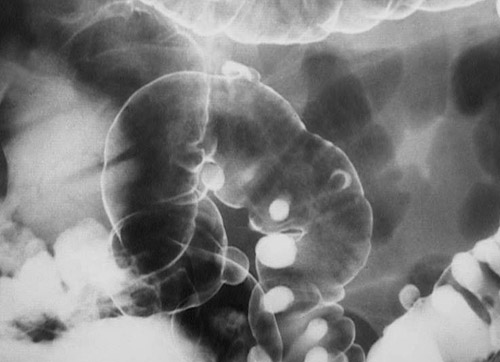

There are multiple outpouchings seen here in this barium enema of the colon, many of which are filled with contrast so that they project outward. These are diverticula, but they are not inflamed.